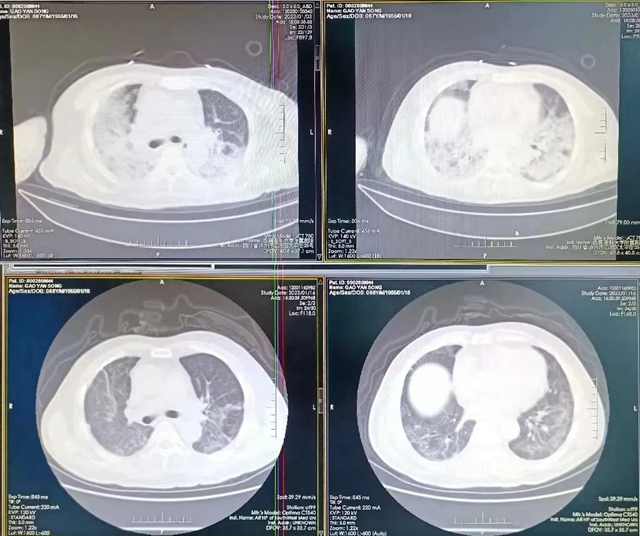

高龄、“白肺”面积超过80%、合并糖尿病、高血压等基础病……手握病危通知书时,家属已做好最坏的打算。然而,在西南医科大学附属医院呼吸与危重症医学科“车轮战”般的精心救治下,李明与高松两位危重症患者竟奇迹康复,氧分压、血氧饱和度、胸部CT等临床各项指标已达到出院标准。

“有糖尿病和高血压病史,入院时呼吸已经相当困难,人已经处于昏迷状态。”呼吸与危重症医学科副主任邓俊副教授仔细检查后发现,高松的肺部感染面积超过80%,血氧饱和度只有50%,呼吸频率43次/分,病情十分危重。

呼吸与危重症医学科主任李玉英教授讲道:目前,呼吸与危重症医学科ICU成功抢救的白肺冠病患者超过90%以上。在治疗上,科室并不是一味照搬新冠治疗手册,而是采取“一人一策”的措施,根据患者年龄、基础病情况、血液指标等給出最佳方案,一边治疗一边调整。最终达到了较好的治疗效果。